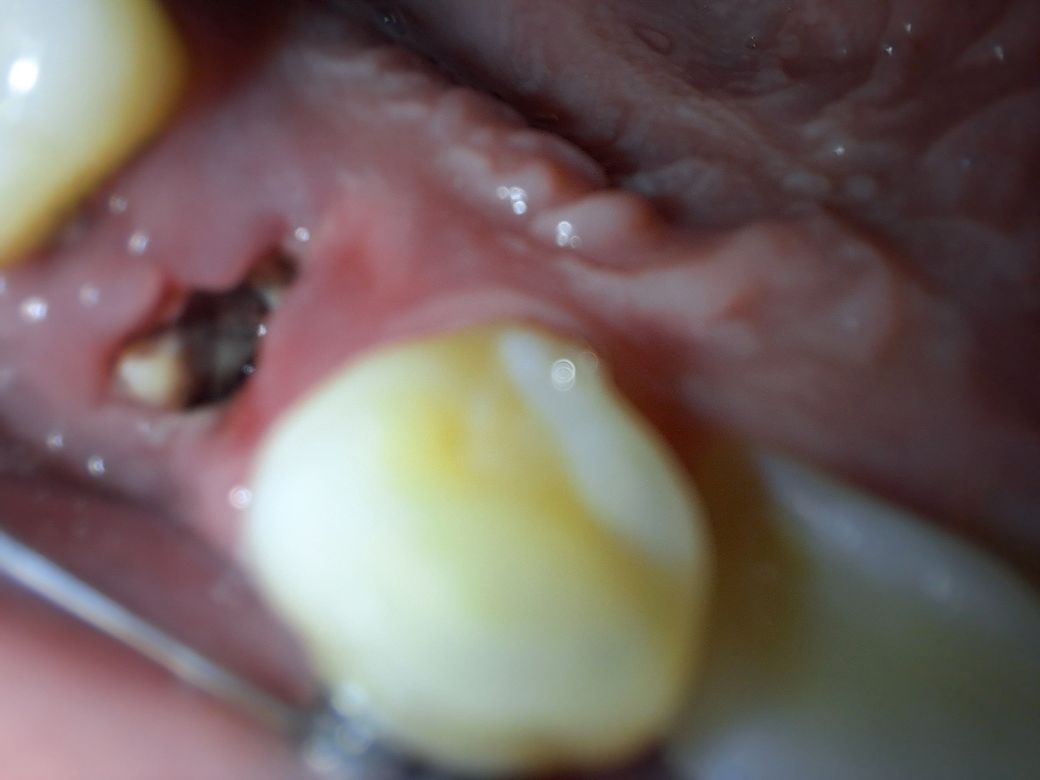

발치후 내부에 뭔가 있습니다.

치아 교정을 위해 발치를 하고 하루하고 좀 더 지났는데 약한 통증이 계속 느껴집니다..반대쪽은 아무 감각도 없고요..

어제 당장에는 안아프던게 오늘 갑자기 통증이 느껴지기 시작하내요.치과를 가는 편이 좋을까요?

발치를 하고 난 뒤에 발치와에 이물질이 들어가서 나오지 않을도 있습니다 .

또한 발치한 부위에 혈병이 떨어져 나가서 내부가 비게 되어도 사진과 같은 모습을 보일수 있습니다.

지금 사진으로 보아 정상적인 치유과정으로 보입니다. 노랗게 보이는 것은 뽑은 자리 부근 잇몸에

딱지 않은 것으로 보면 됩니다. 통증이 약간 있으면 진통제 복용하시고 심한 통증이 있으면 염증을 의심해야

하니 도로 치과 내원하는 것이 좋습니다.

사진이 흐려서 정확히 보이질 않아 판단이 어렵습니다.

노란것은 음식물일수도 있고, 잇몸의 일부일수도 있습니다. 우선 정확히 봐야 판단이 가능하기 때문에, 통증이 몇일 지속된다면 치과에 방문해보시기 바랍니다. 감사합니다.